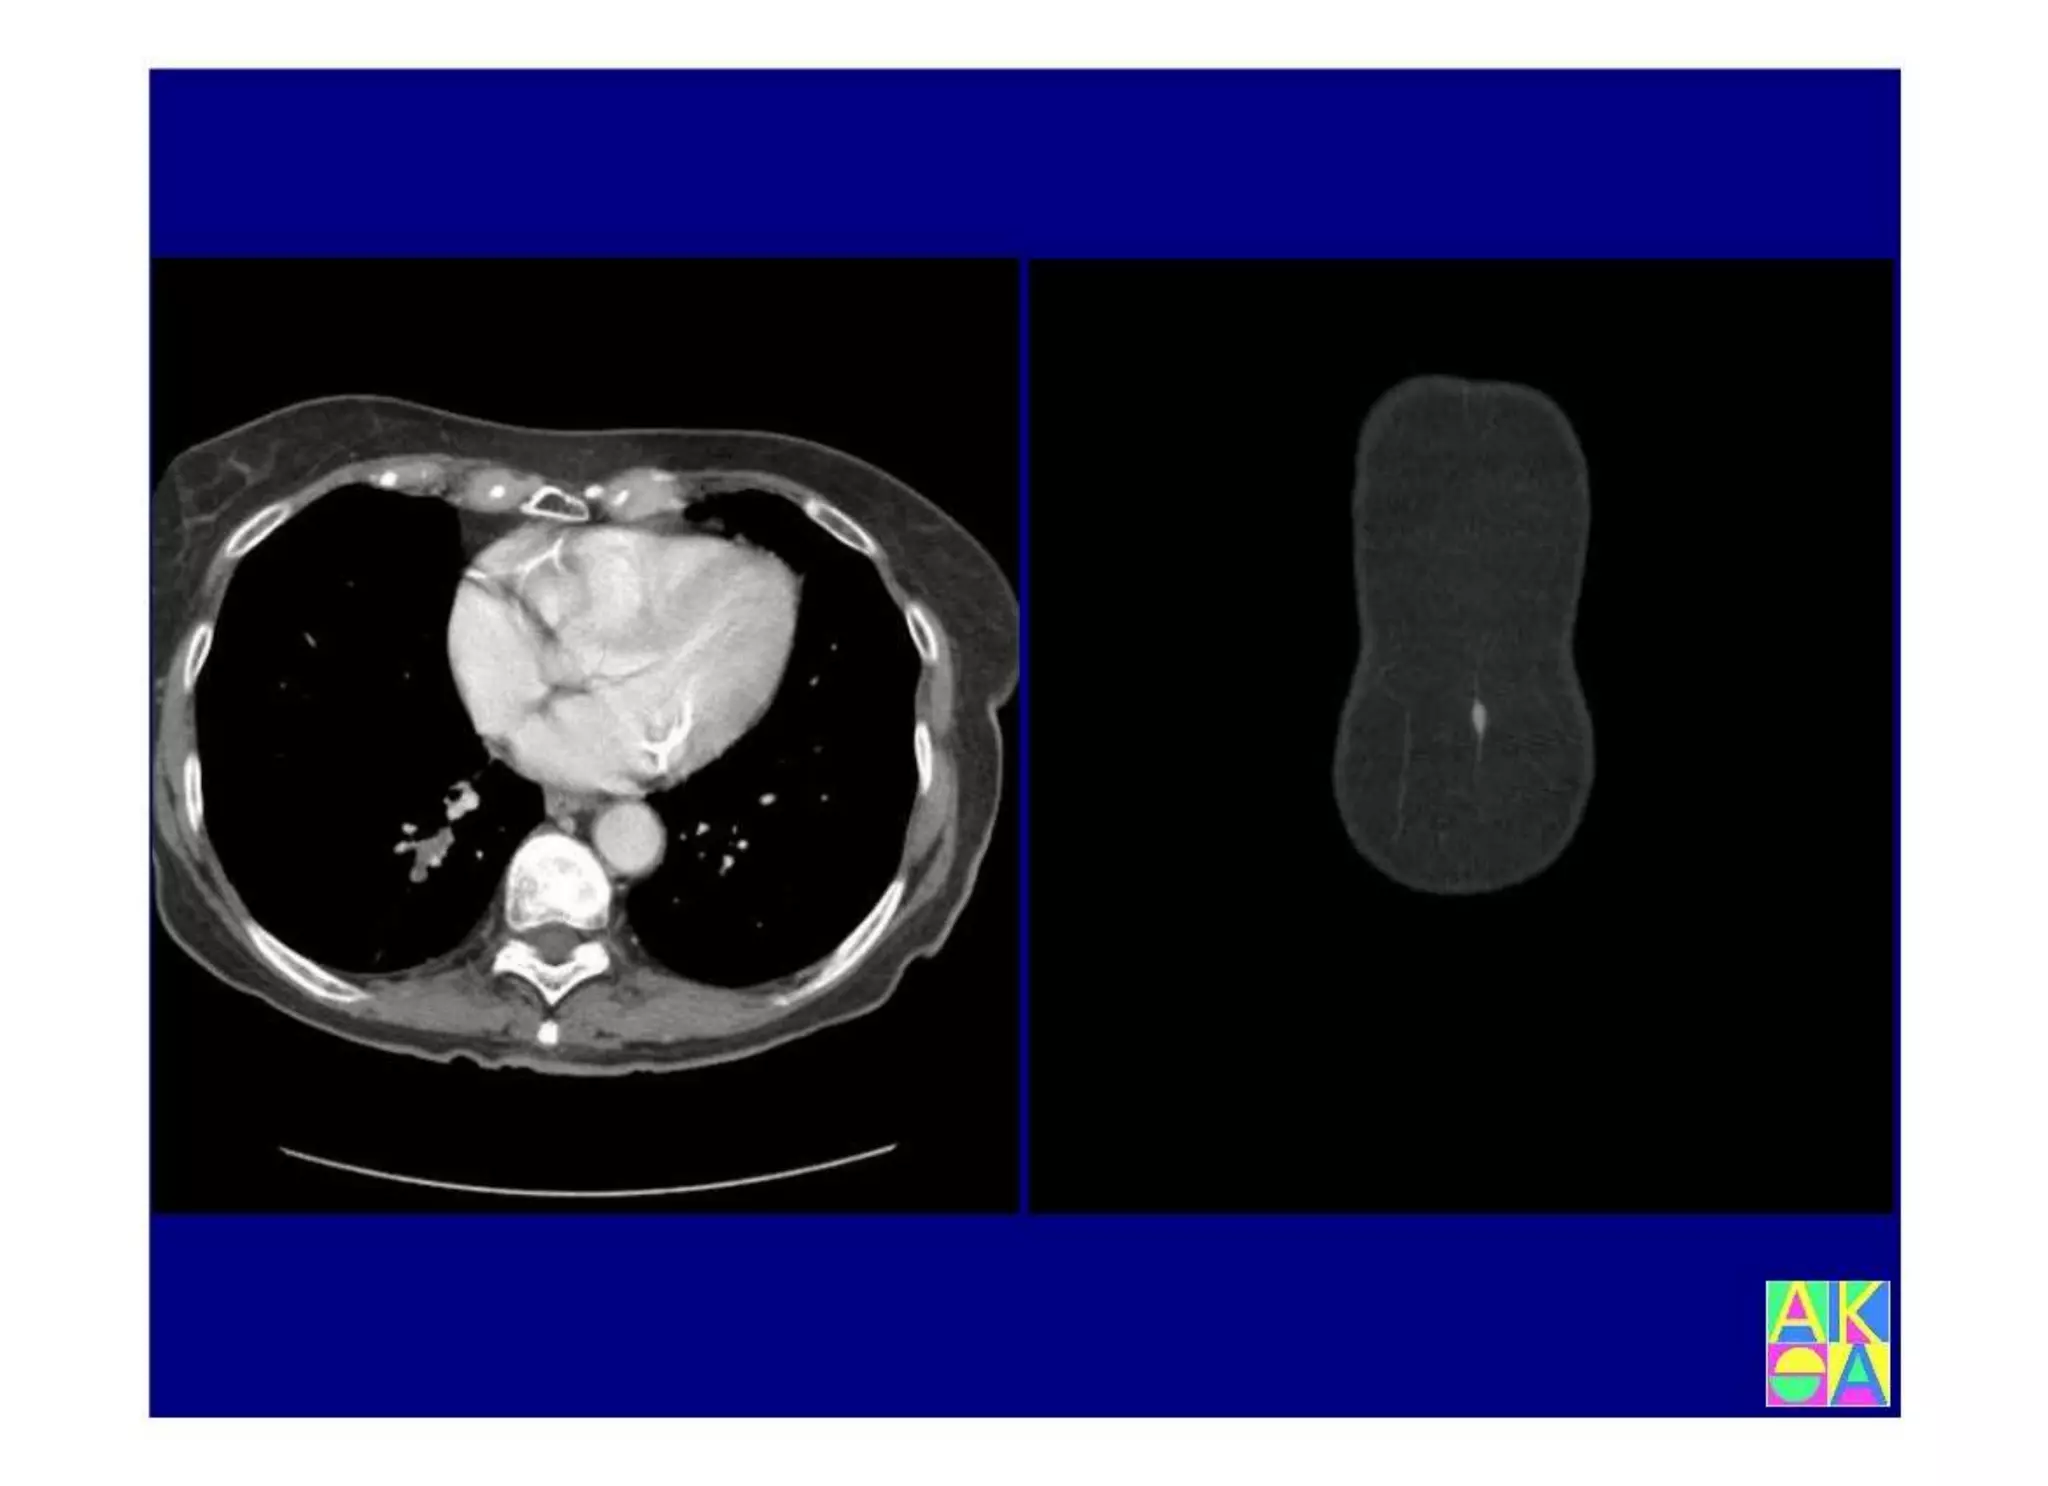

Chronische Enteropathie und Ileus, Dünndarm und Dickdarmdiagnostik, Mechanischer und paralytischer Ileus, Eingeklemmte Darmabschnitte, aufgereihter Bridenileus, und dazu Dickdarmileus, eingeklemmte Hernien, Weitergabeskript